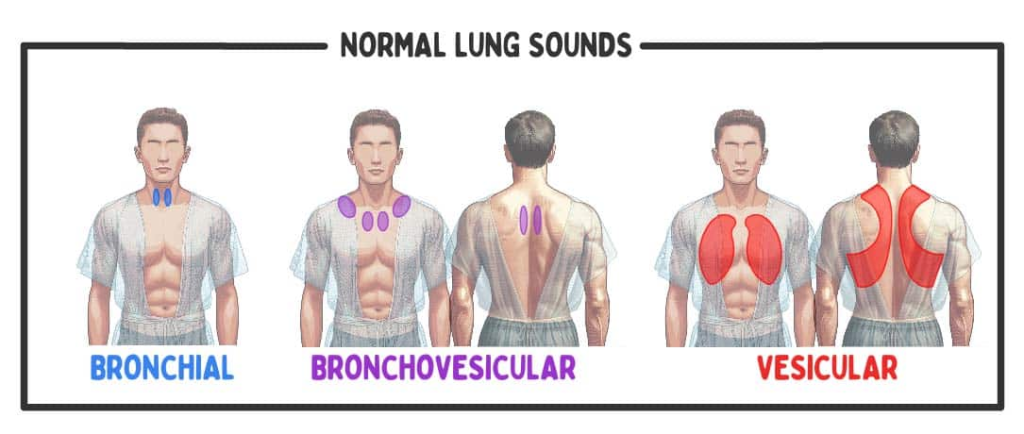

Auscultation (અસ્કલટેશન):

- અસ્કલટેશનમાં સ્ટેથોસ્કોપની મદદથી લંગ સાઉન્ડ સાંભળવામાં આવે છે.

- સ્ટેથોસ્કોપની મદદથી નોર્મલ લંગ સાઉન્ડની કેરેક્ટરિસ્ટિક નોટ કરવી જેમ કે લોકેશન, ક્વોલિટી, ઇન્ટેન્સિટી

- અસ્કલટેશનમાં ચેસ્ટની એન્ટેરિયર અને પોસ્ટેરીયર બાજુ ડાયાફ્રામની મદદથી લંગ સાઉન્ડ અસ્કલટેટ કરવામાં આવે છે. નીચે આપેલા પિક્ચરમાં દર્શાવ્યા મુજબ ચેસ્ટને અસ્કલટેટ કરવામાં આવે છે.

Normal lung sound (નોર્મલ લંગ સાઉન્ડ):

- બ્રોન્કીઅલ સાઉન્ડ (Bronchial Sound), વેસિક્યુલર સાઉન્ડ (Vesicular Sound) અને બ્રોન્કો-વેસિક્યુલર સાઉન્ડ (Bronchovesicular Sound) એ નોર્મલ લંગ સાઉન્ડ છે.

Bronchial sound (બ્રોન્કીઅલ સાઉન્ડ):

- બ્રોન્કીઅલ એ નોર્મલ હાઇપીચ હોલો અથવા ટ્યુબ્યુલર સાઉન્ડ છે.

- ટ્રકિયાના ભાગમાં સાંભળવા મળે છે.

- જેમાં ઇન્સ્પાયરેટરી ટાઇમ કરતા એક્સપાયરેટરી ટાઇમ વધારે હોય છે.

Vesicular sound (વેસિક્યુલર સાઉન્ડ):

- વેસેક્યુલર એ નોર્મલ લોપીચ સોફ્ટ સાઉન્ડ છે. જે એન્ટાઇર લંગમાં સાંભળવા મળે છે.

- જેમાં એક્સપાયરેટરી કરતાં ઇન્સ્પાયરેટરી ટાઇમ વધારે જોવા મળે છે.

Bronchovesicular sound (બ્રોન્કો-વેસિક્યુલર સાઉન્ડ):

- બ્રોન્કો-વેસિક્યુલર એ નોર્મલ મીડીયમ પીચ સાઉન્ડ છે જેમાં ઇન્સ્પાયરેટરી અને એક્સપાયરી ટાઈમ સરખો જોવા મળે છે.